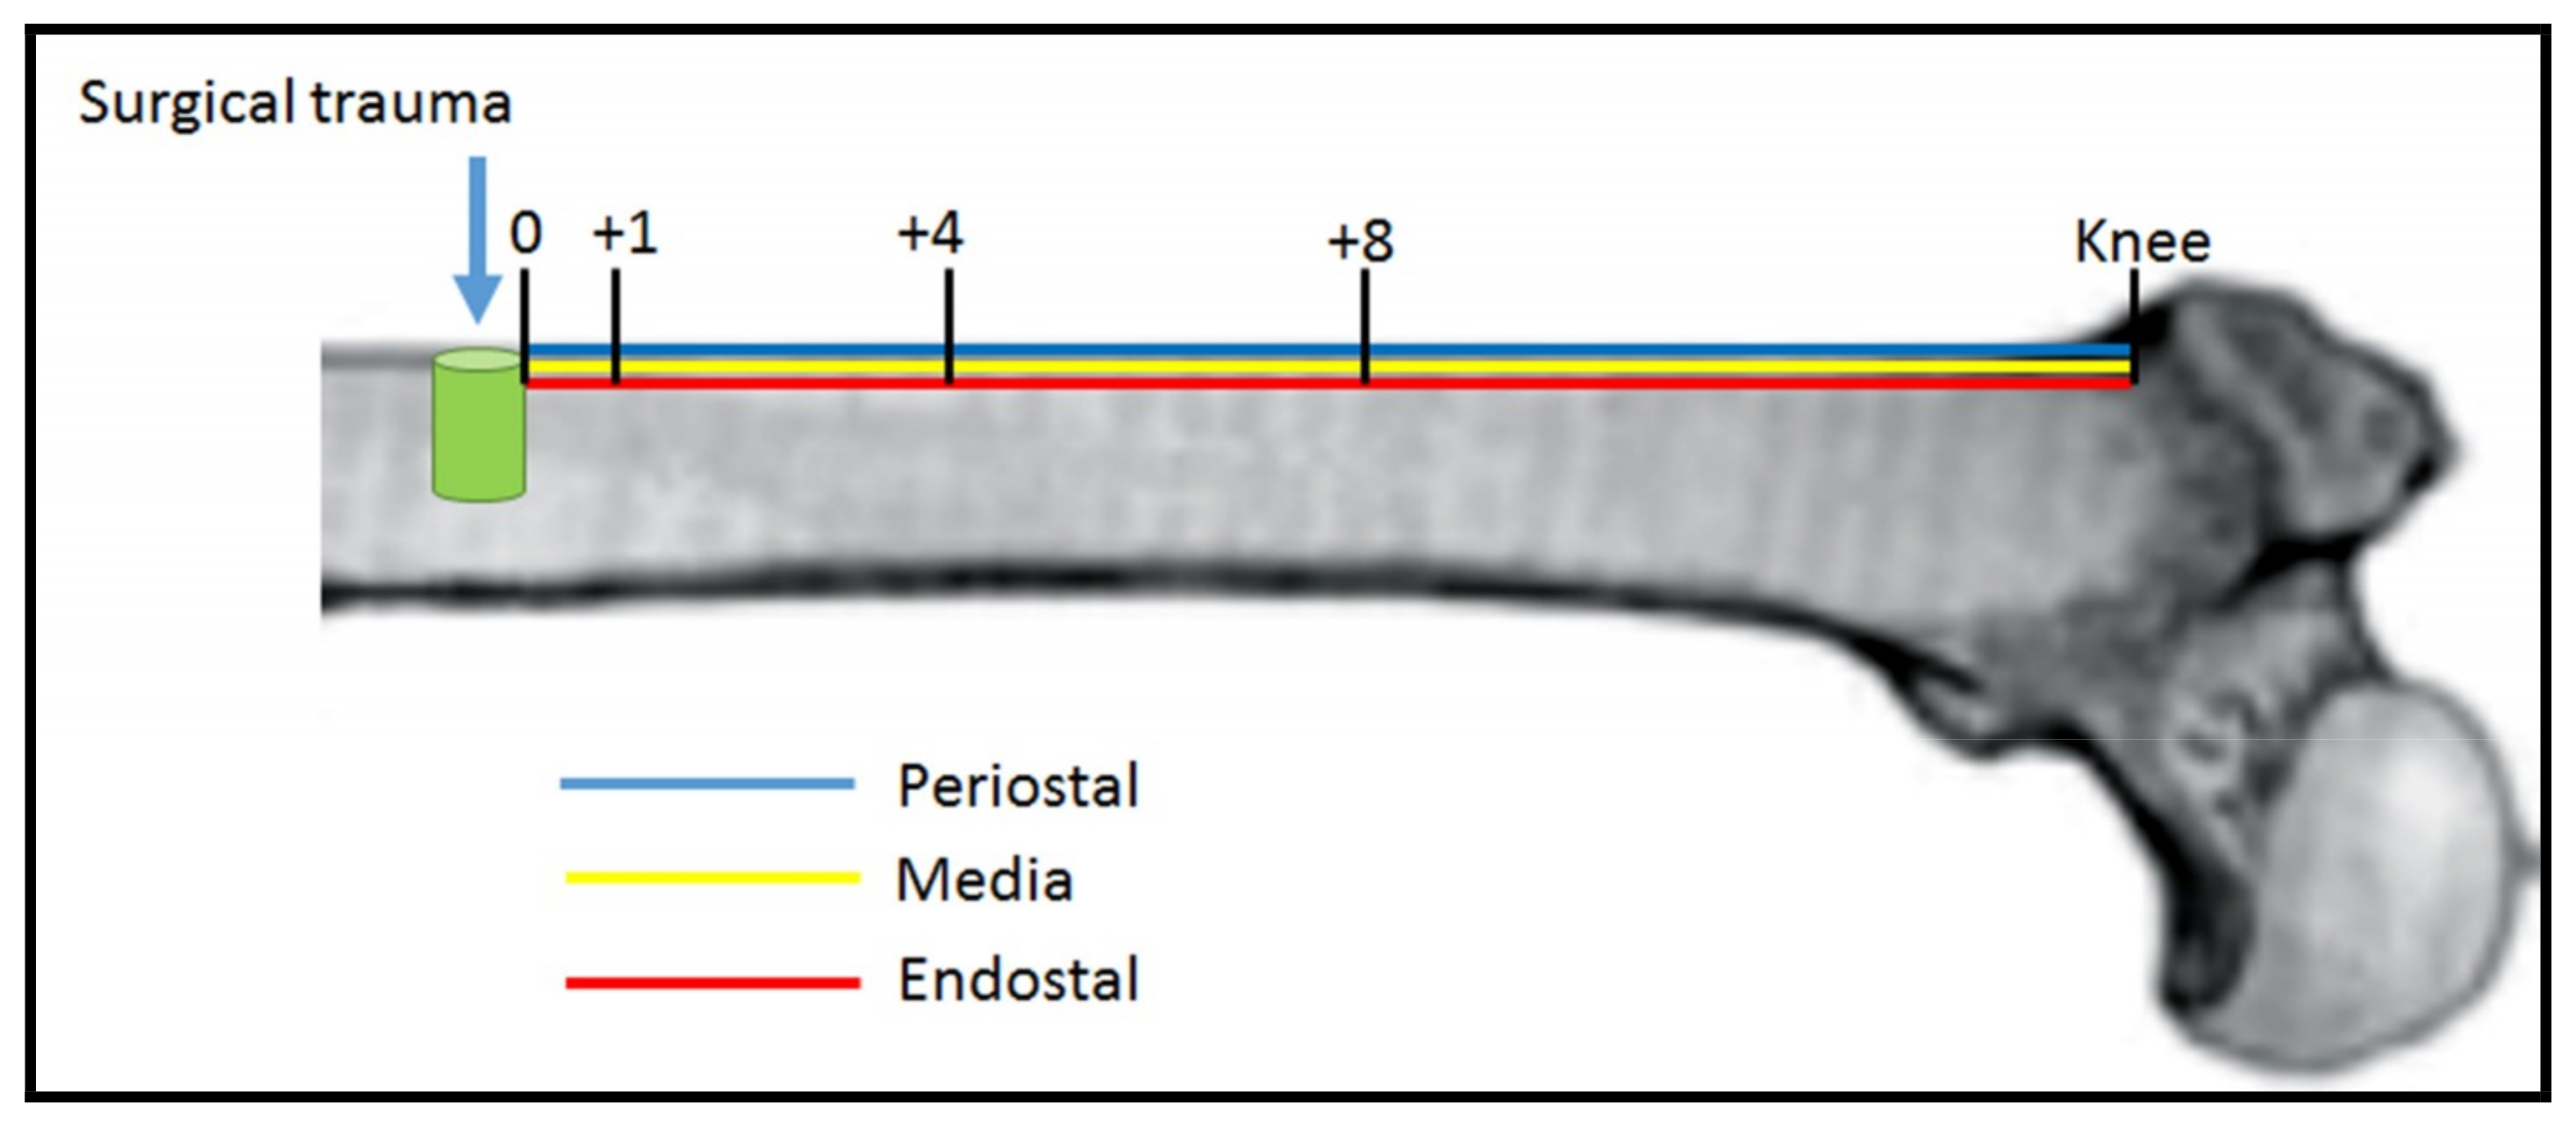

2.3. Animals Surgery

2.6. Data Collect